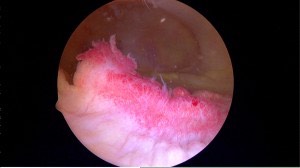

The normal knee joint

Smooth Cartilage seen in the normal non-arthritis knee joint.

Arthroscopic view showing the rough cartilage surface found in arthritis

Knee arthritis is a progressive wearing out of the normal articular cartliage that lines the moving surfaces of the knee. As the cartilage wears away it can become frayed and rough, and the thickness of the protective cartilage decreases. This wear and tear can be a slow and progressive process or can develop because of a prior injury. As the arthritic process progresses it can result in bone rubbing on bone, and become progressively more painful. The “environment” in an arthritic knee allows the “breaking down” (catabolic effect) process of the cartilage and meniscus to continue. The wear and tear cycle just continues until the knee is completely worn out.